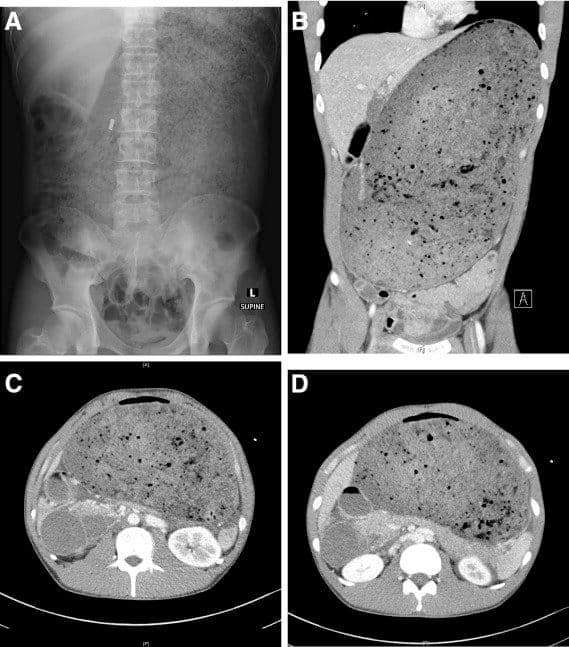

Curso avanzado SIRT. Desengranando la Radioembolización con el gran equipo multidisciplinar del H. Gregorio Marañón Sirtex Medical